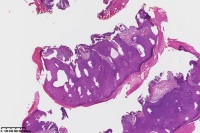

汗孔瘤?

性别

女

年龄

50岁

足底丘疹

汗孔瘤。